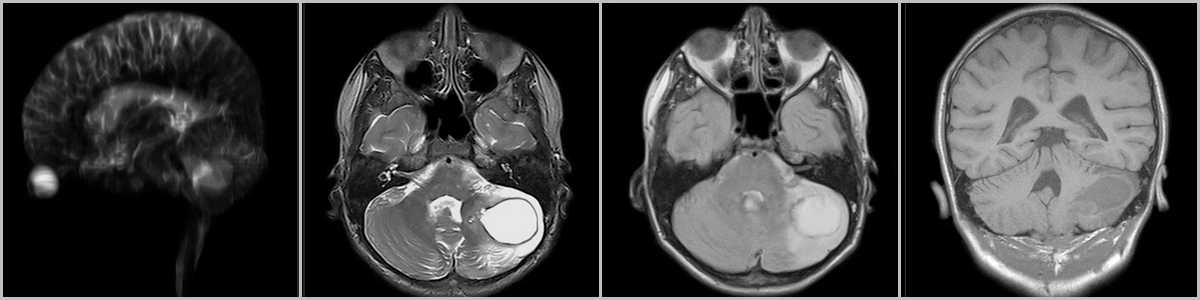

Гемангиобластома

Гемангиобластома — кистозная опухоль с мелким пристеночным узлом, располагается инфратенториально, может встречаться интрамедуллярно в спинном мозге, ассоциирована с болезнью фон Гиппеля-Линдау, при которой обнаруживается поражение других органов и систем, в частности почек (поликистоз) и надпочечников (феохромоцитома). При перфузионном исследовании отмечается выраженное превалирование показателей гемодинамики (rCBF и rCBV) у гемангиобластомы над пилоцитарной астроцитомой . Кроме того, астроцитома встречается чаще у детей и подростков, а гемангиобластома — у взрослых.

Рис.10 * Рис. 10 был заимствован из “Диагностическая нейрорадиология” 2009г. Корниенко В.Н., Пронин И.Н. 2009г. с целью наглядной демонстрации патологического процесса.

Мелкая гемангиобластома в области левой мозжечковой миндалины (стрелка на рис.10). После внутривенного контрастирования происходит интенсивное накопление контраста в пристеночном сосочке (стрелка на рис.10). Объёмный мозговой кровоток гемангиобластомы (стрелка на рис.10) существенно превышает те же показатели пилоцитарной астроцитомы (головка стрелки на рис.10).